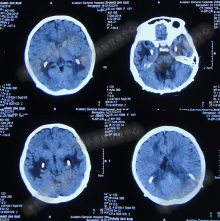

2014年8月31日住入李小勇脑脊液中心,入院时:卧床,表情淡漠,神志嗜睡;体温高37.9°C;头颅枕后正中手术瘢痕,结痂尚未脱落;左枕侧脑室外引流固定在位,尚通畅,可见淡红色浑浊脑脊液引出;颈抵抗,双肺呼吸音粗(图-27);头部CT检查示(小脑肿瘤术后颅内感染病例)脑室系统粘连严重伴双侧颞角脑室扩张明显,双侧侧脑室见引流管影,脑内见多发斑片低密度,中线结构无移位,颅骨术后改变(图-28)。

图-27:2014年8月31日入院时

图-28:2014年8月31日头部CT